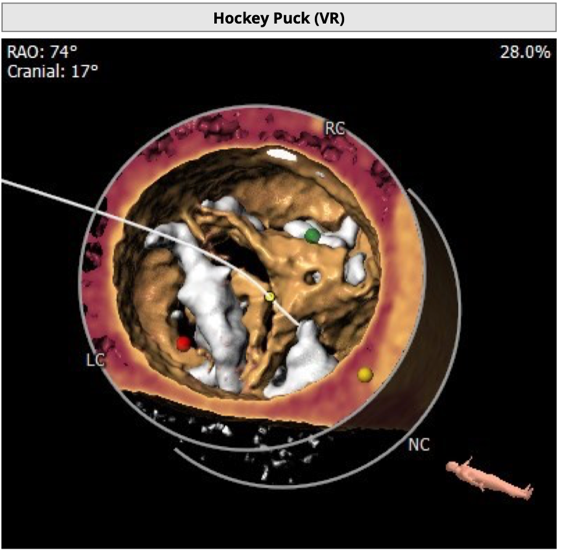

主动脉根部评估

CT 数据显示该患者为Type1型二叶式主动脉瓣

主动脉瓣瓣环周长76.8mm,周长径24.5mm;

LVOT 周长 86.1mm,周长径27.4mm;

SOV:32.3mm*34.5mm*33.7mm;

STJ 周长 100.6mm;

瓣叶严重粘连增厚,瓣叶钙化明显,HU850:1448.3mm³。

左冠开口高度8.6mm,右冠开口高度15.0mm,左冠高度偏低,左冠瓣瓣尖钙化明显,根据瓦氏窦内径和瓣叶长度综合判断,左冠存在较高堵塞风险;左心室后壁增厚。